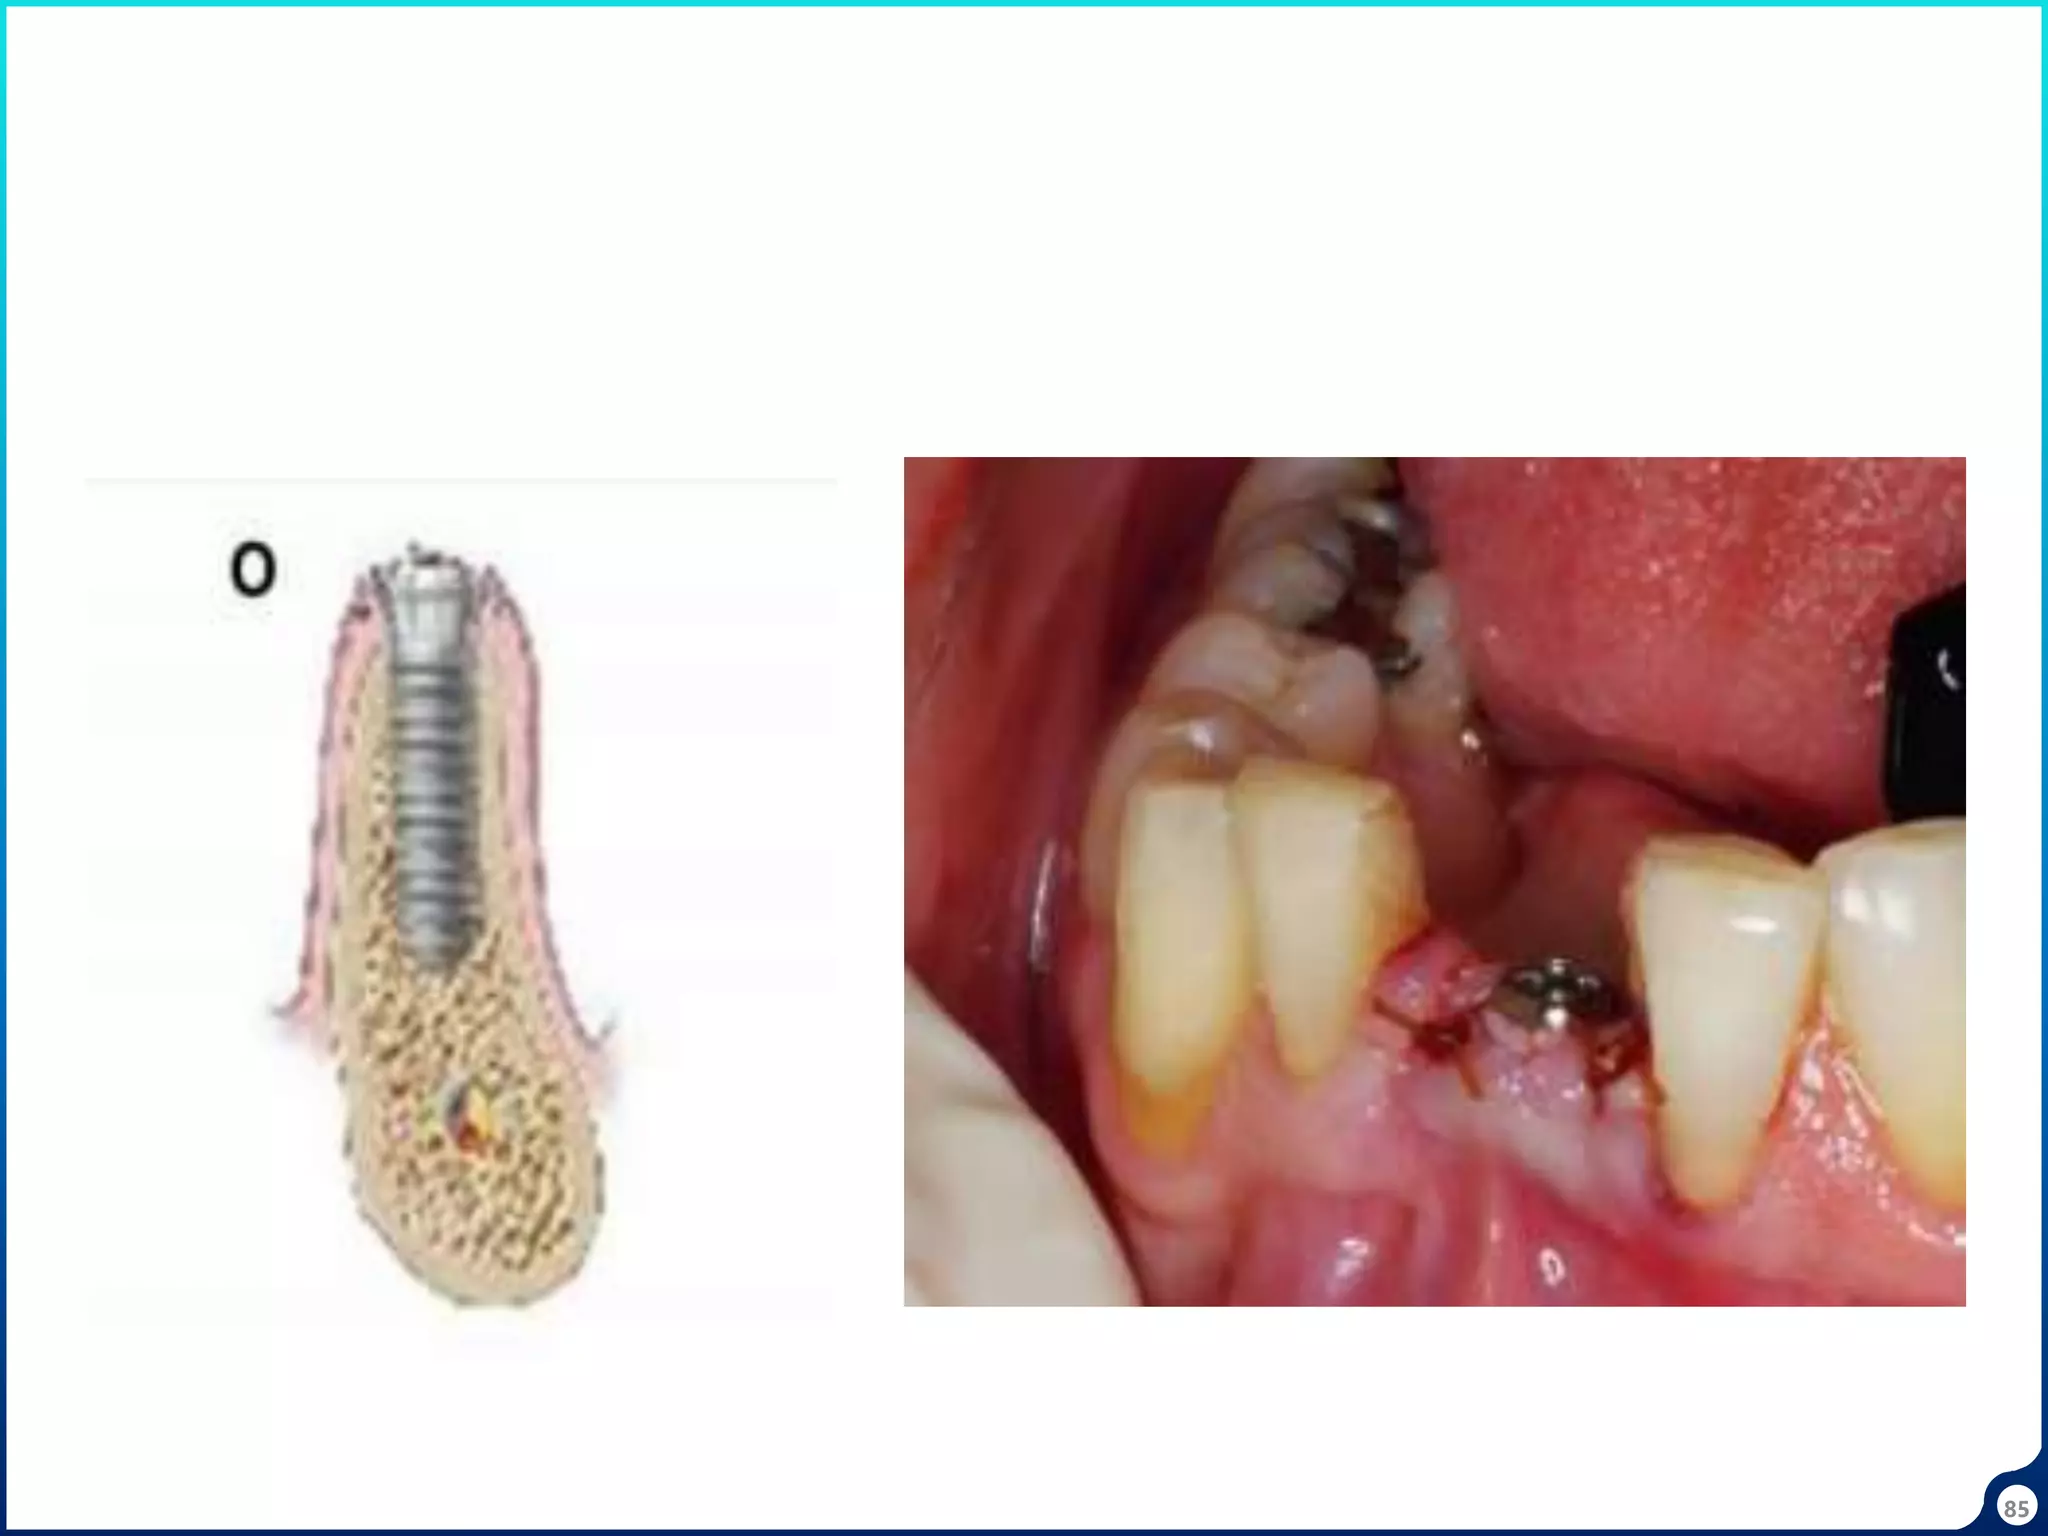

• Root is bisected.

• Buccal 2/3rd of root is preserved in the socket

• Periodontium along with bundle bone remain intact.

• Buccal bone remains intact

Socket shield